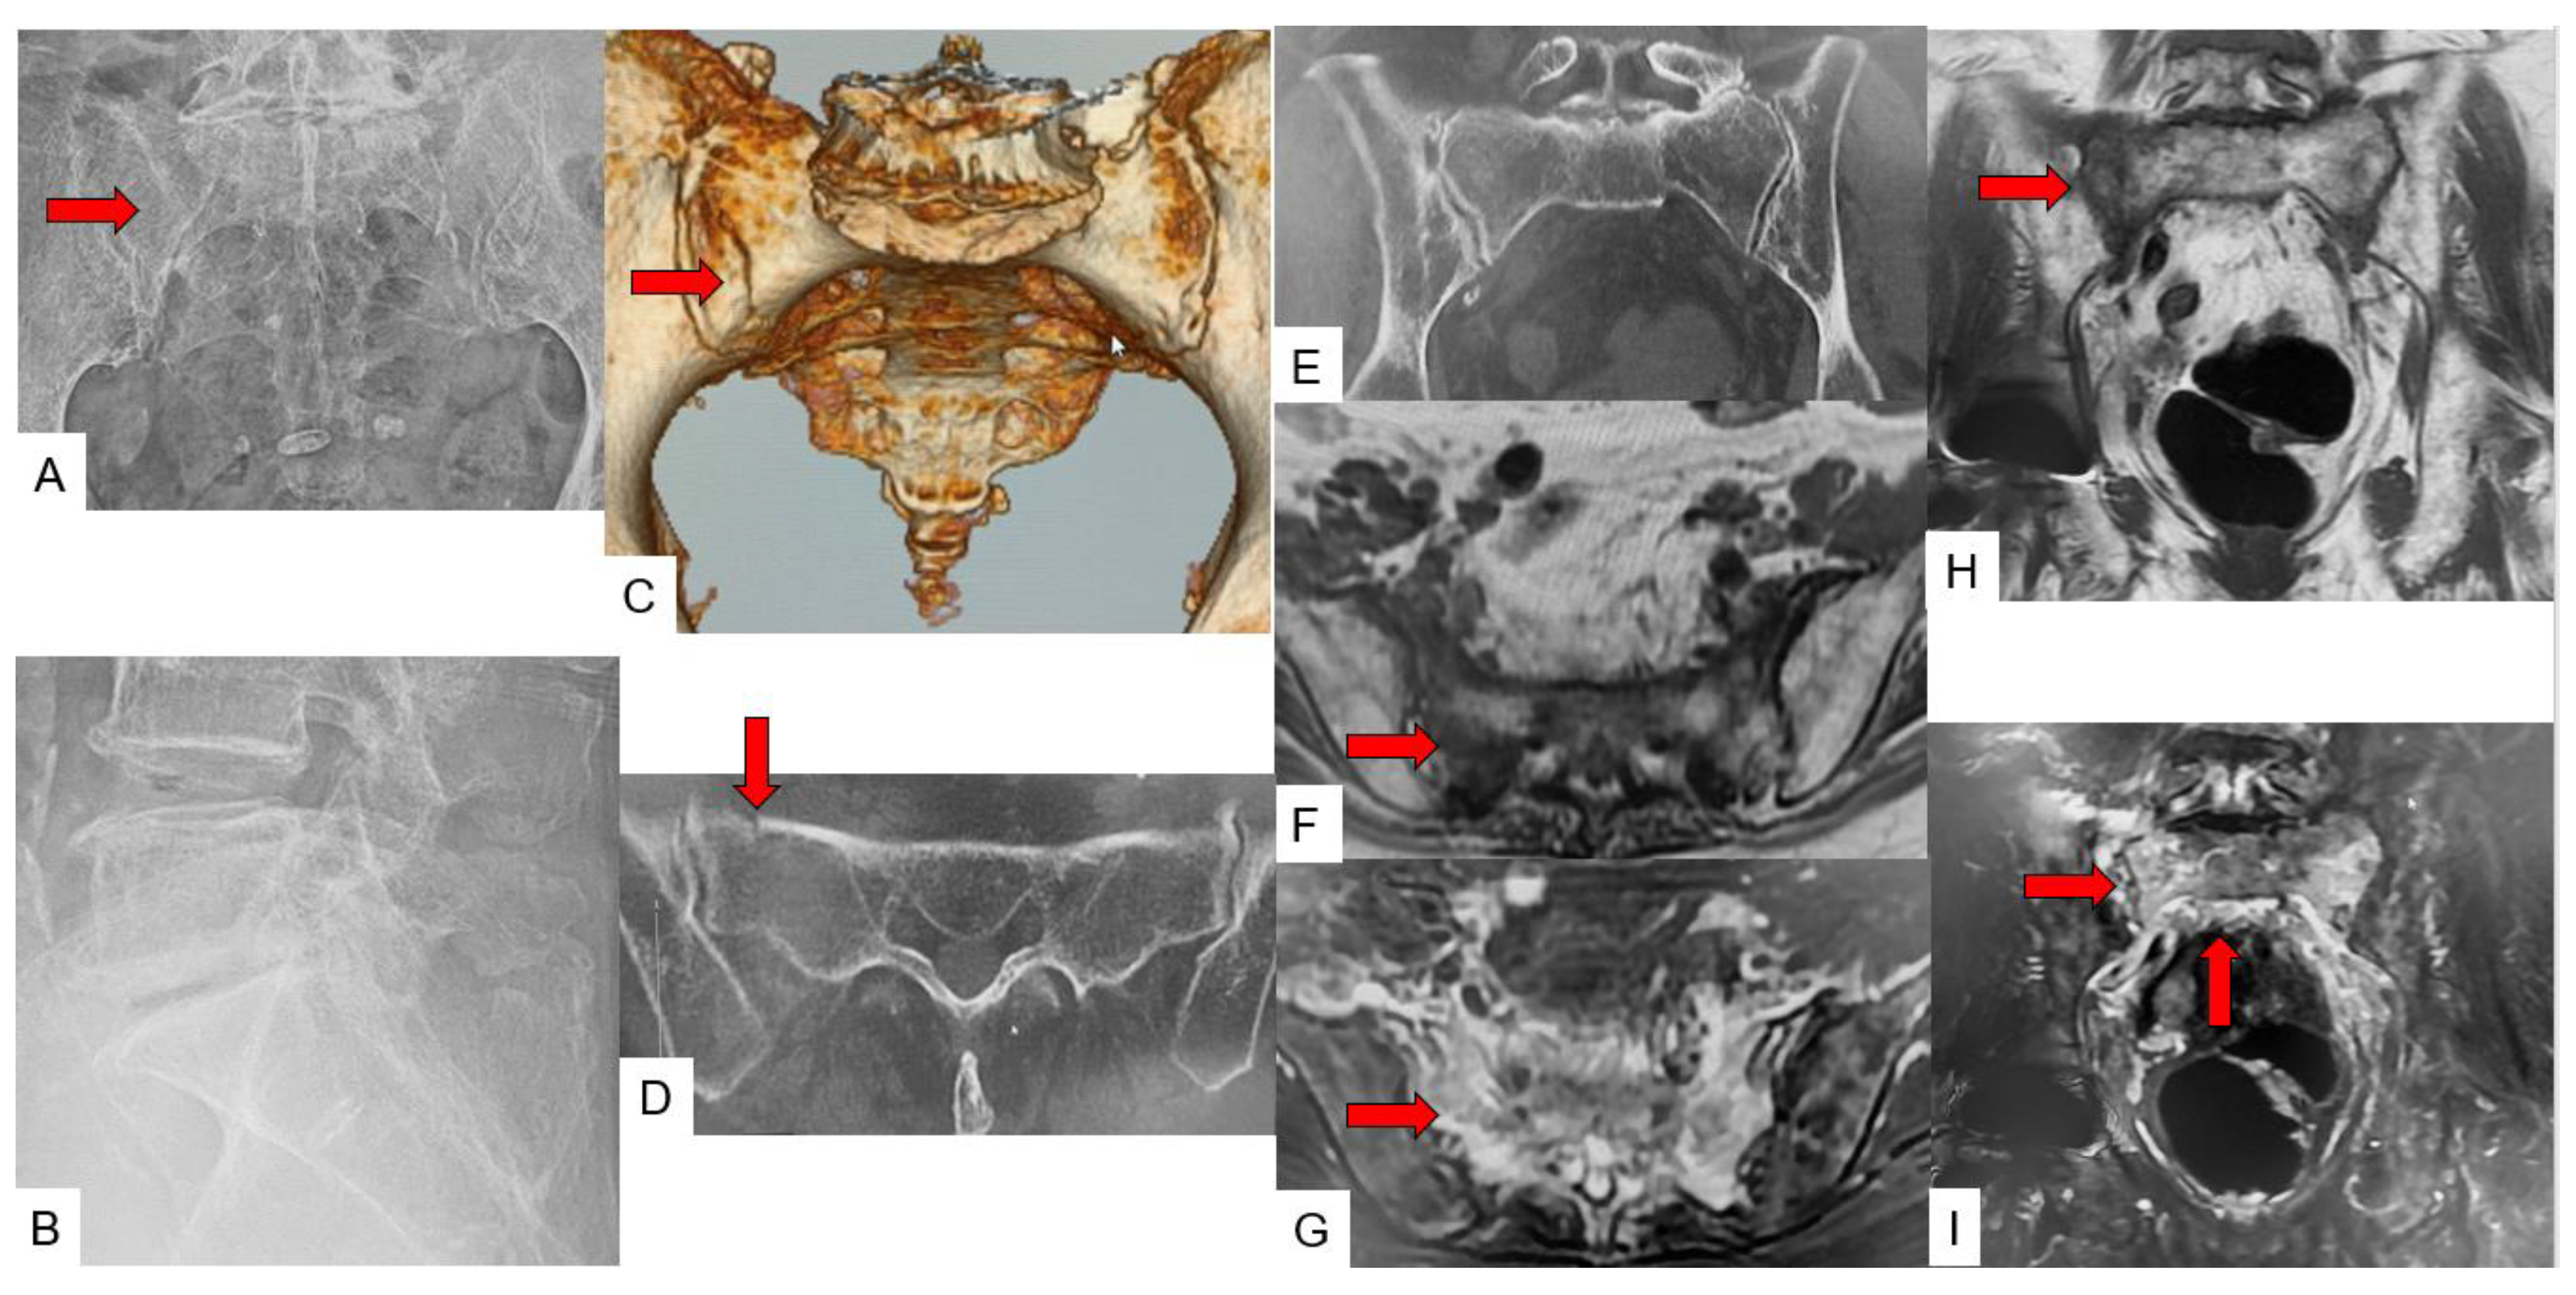

3.3. SIF Fracture Pattern

3.4. Typical SIF Case